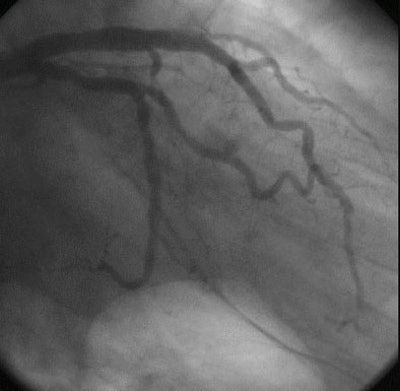

In images of a 62-year-old patient who underwent a heart transplant in 1999 due to cardiomyopathy, a heart rate of 115 bpm did not render the CT data nondiagnostic.

On CT "we observed on the axial images mixed plaque in the distal portion of the main LAD (left anterior descending), calcified soft plaque … at the LAD, and correlation between (CT and) IVUS where we observed the soft portion of the plaque," Carrascosa said. "On digital angiography we cannot determine any stenosis on distal portion of main LAD so this is a negative finding for conventional angiography in correlation with (MDCT)."

| Top to bottom: Endothelial proliferation in a transplant patient. Above, normal digital angiography . Below, MDCT multiplanar curved reformation of left main artery and left anterior descending artery; arrow points to area of endothelial proliferation. Next, IVUS followed by (bottom) axial CT image at the same level demonstrating endothelial proliferation. All images courtesy of Dr. Patricia Carrascosa. |

In a second example, a 60-year-old patient who underwent a heart transplant in 2000 due to systemic cardiomyopathy had subtle endothelial proliferation in the artery that could be seen in the multiplanar reformatted image of the right cerebral artery, which was correlated to the IVUS images. The intimal proliferation "does not produce stenosis, but it's diffuse and we see the vessel with (a smaller) diameter," Carrascosa said.